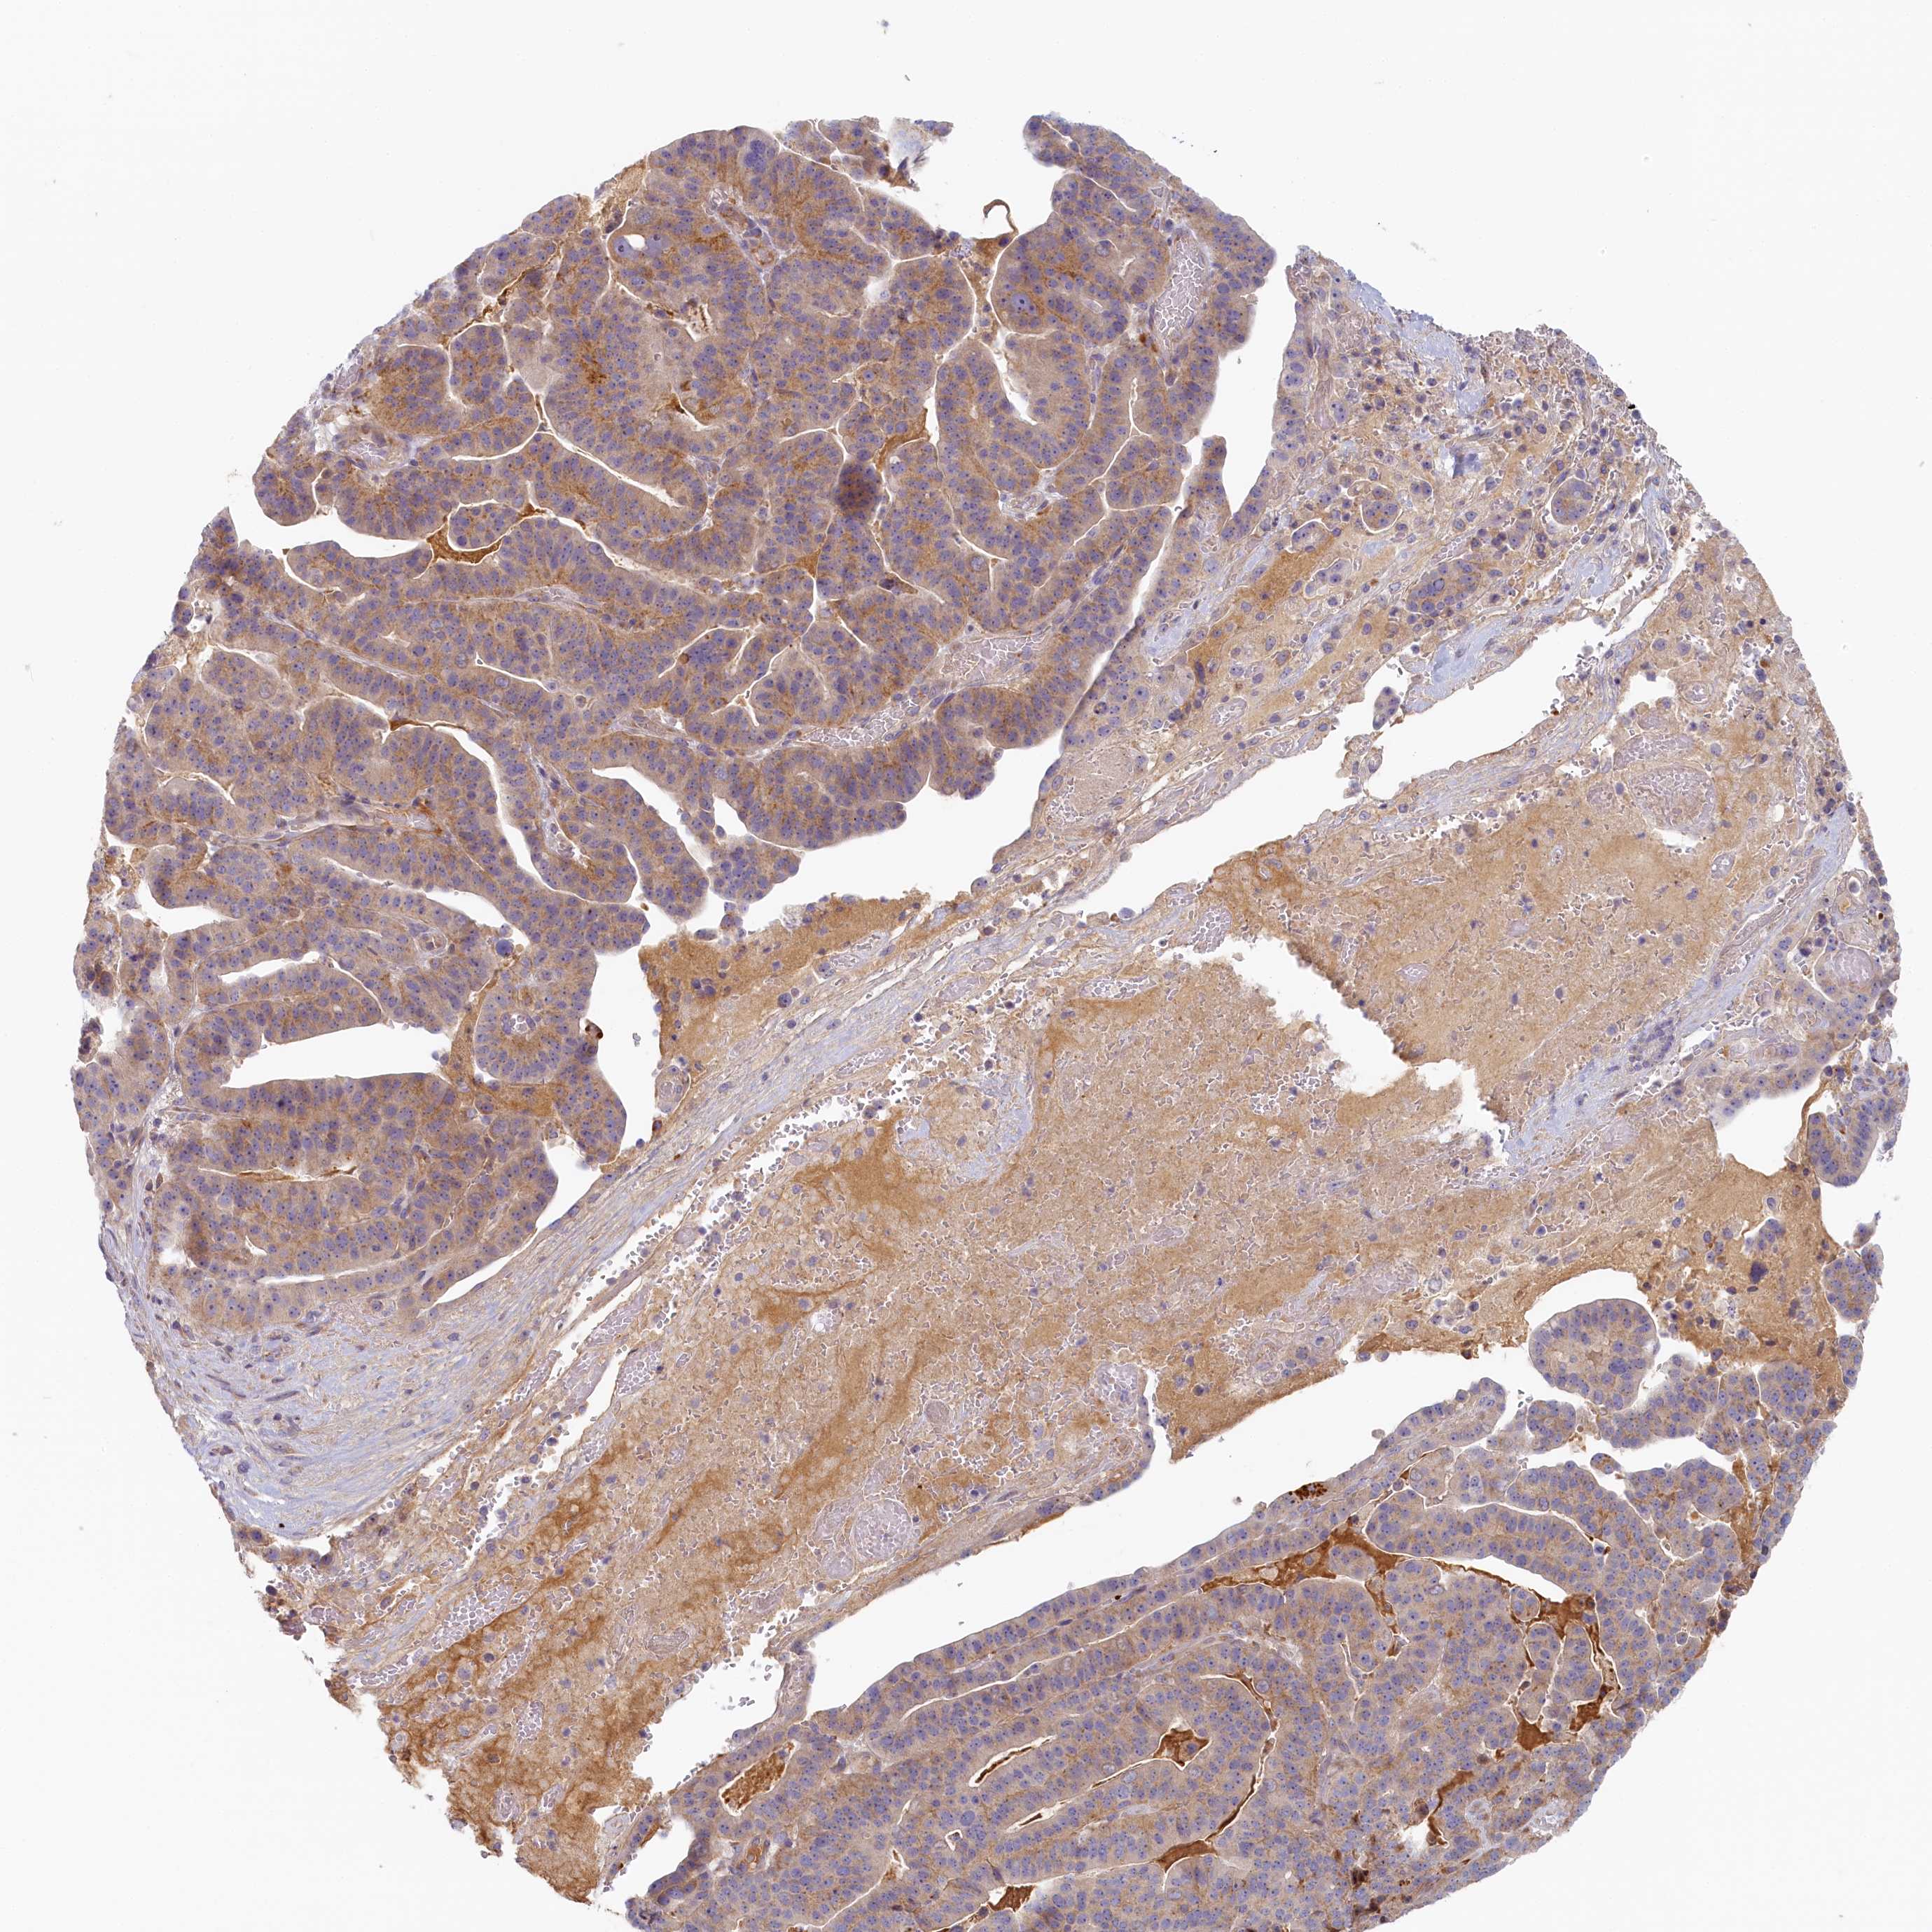

STOMACH CANCER - Protein expressioni

A mouse-over function shows sample information and annotation data. Click on an image to view it in a full screen mode. Samples can be filtered based on level of antibody staining by selecting one or several of the following categories: high, medium, low and not detected. The assay and annotation is described here.

Note that samples used for immunohistochemistry by the Human Protein Atlas do not correspond to samples in the TCGA dataset.

Antibody stainingi

Antibody staining in the annotated cell types in the current human tissue is reported as not detected, low, medium, or high, based on conventional immunohistochemistry profiling in selected tissues. This score is based on the combination of the staining intensity and fraction of stained cells.

Each image is clickable and will lead to virtual microscopy that enables deeper exploration of all samples and also displays staining intensity scores, fraction scores and subcellular localization as well as patient and tissue information for each sample.

Antibody HPA041019

Antibody HPA042033

Staining

High

Medium

Low

Not detected

Intensity

Strong

Moderate

Weak

Negative

Quantity

>75%

75%-25%

<25%

None

Location

Nuclear

Cytoplasmic/membranous

Cytoplasmic/membranous,nuclear

Adenocarcinoma, NOS